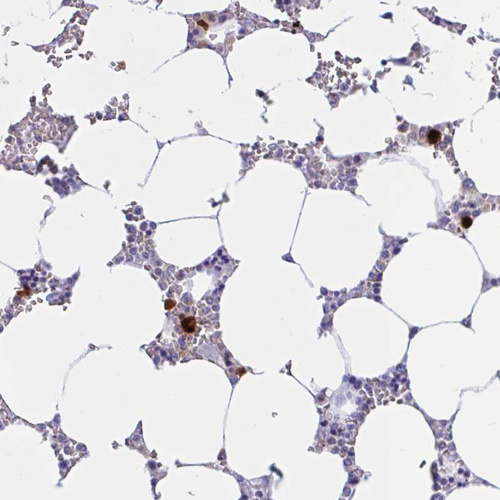

Immunohistochemistry analysis in human bone marrow and skeletal muscle tissues using HPA056183 antibody. Corresponding RNASE3 RNA-seq data are presented for the same tissues.